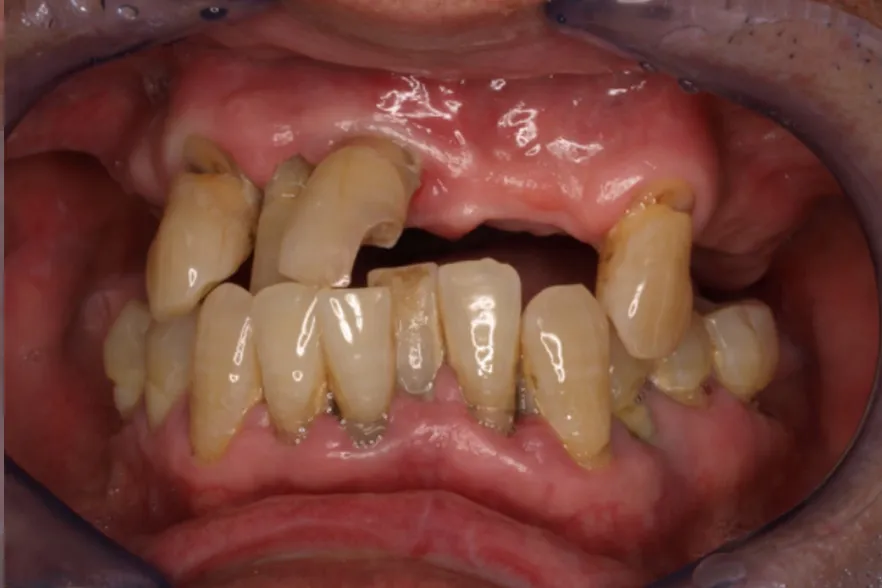

Before

治療内容 | 口腔内診査〜カウンセリング 歯周初期治療 インプラント埋入 歯周外科治療 仮歯にてインプラントを含めた咬む位置の決定 最終的な被せ物(メタルセラミックスクラウン)の型取り〜装着 |

治療期間 | 2年半 |

治療回数 | 約80回 |

リスク | 手術、並びに治療における疼痛 連結をしている歯が二次的な虫歯、歯周病になりやすくなる 今後のメンテナンスが必須となる |

費用(税込) | 約¥4,950,000 |